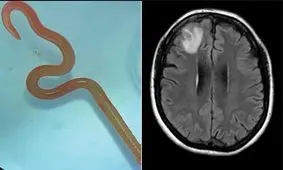

محققان دریافتند که نورونهای مغز در هنگام خواب امواجی را شلیک میکنند که ضایعات مغزی را که در ساعات بیداری انباشته…